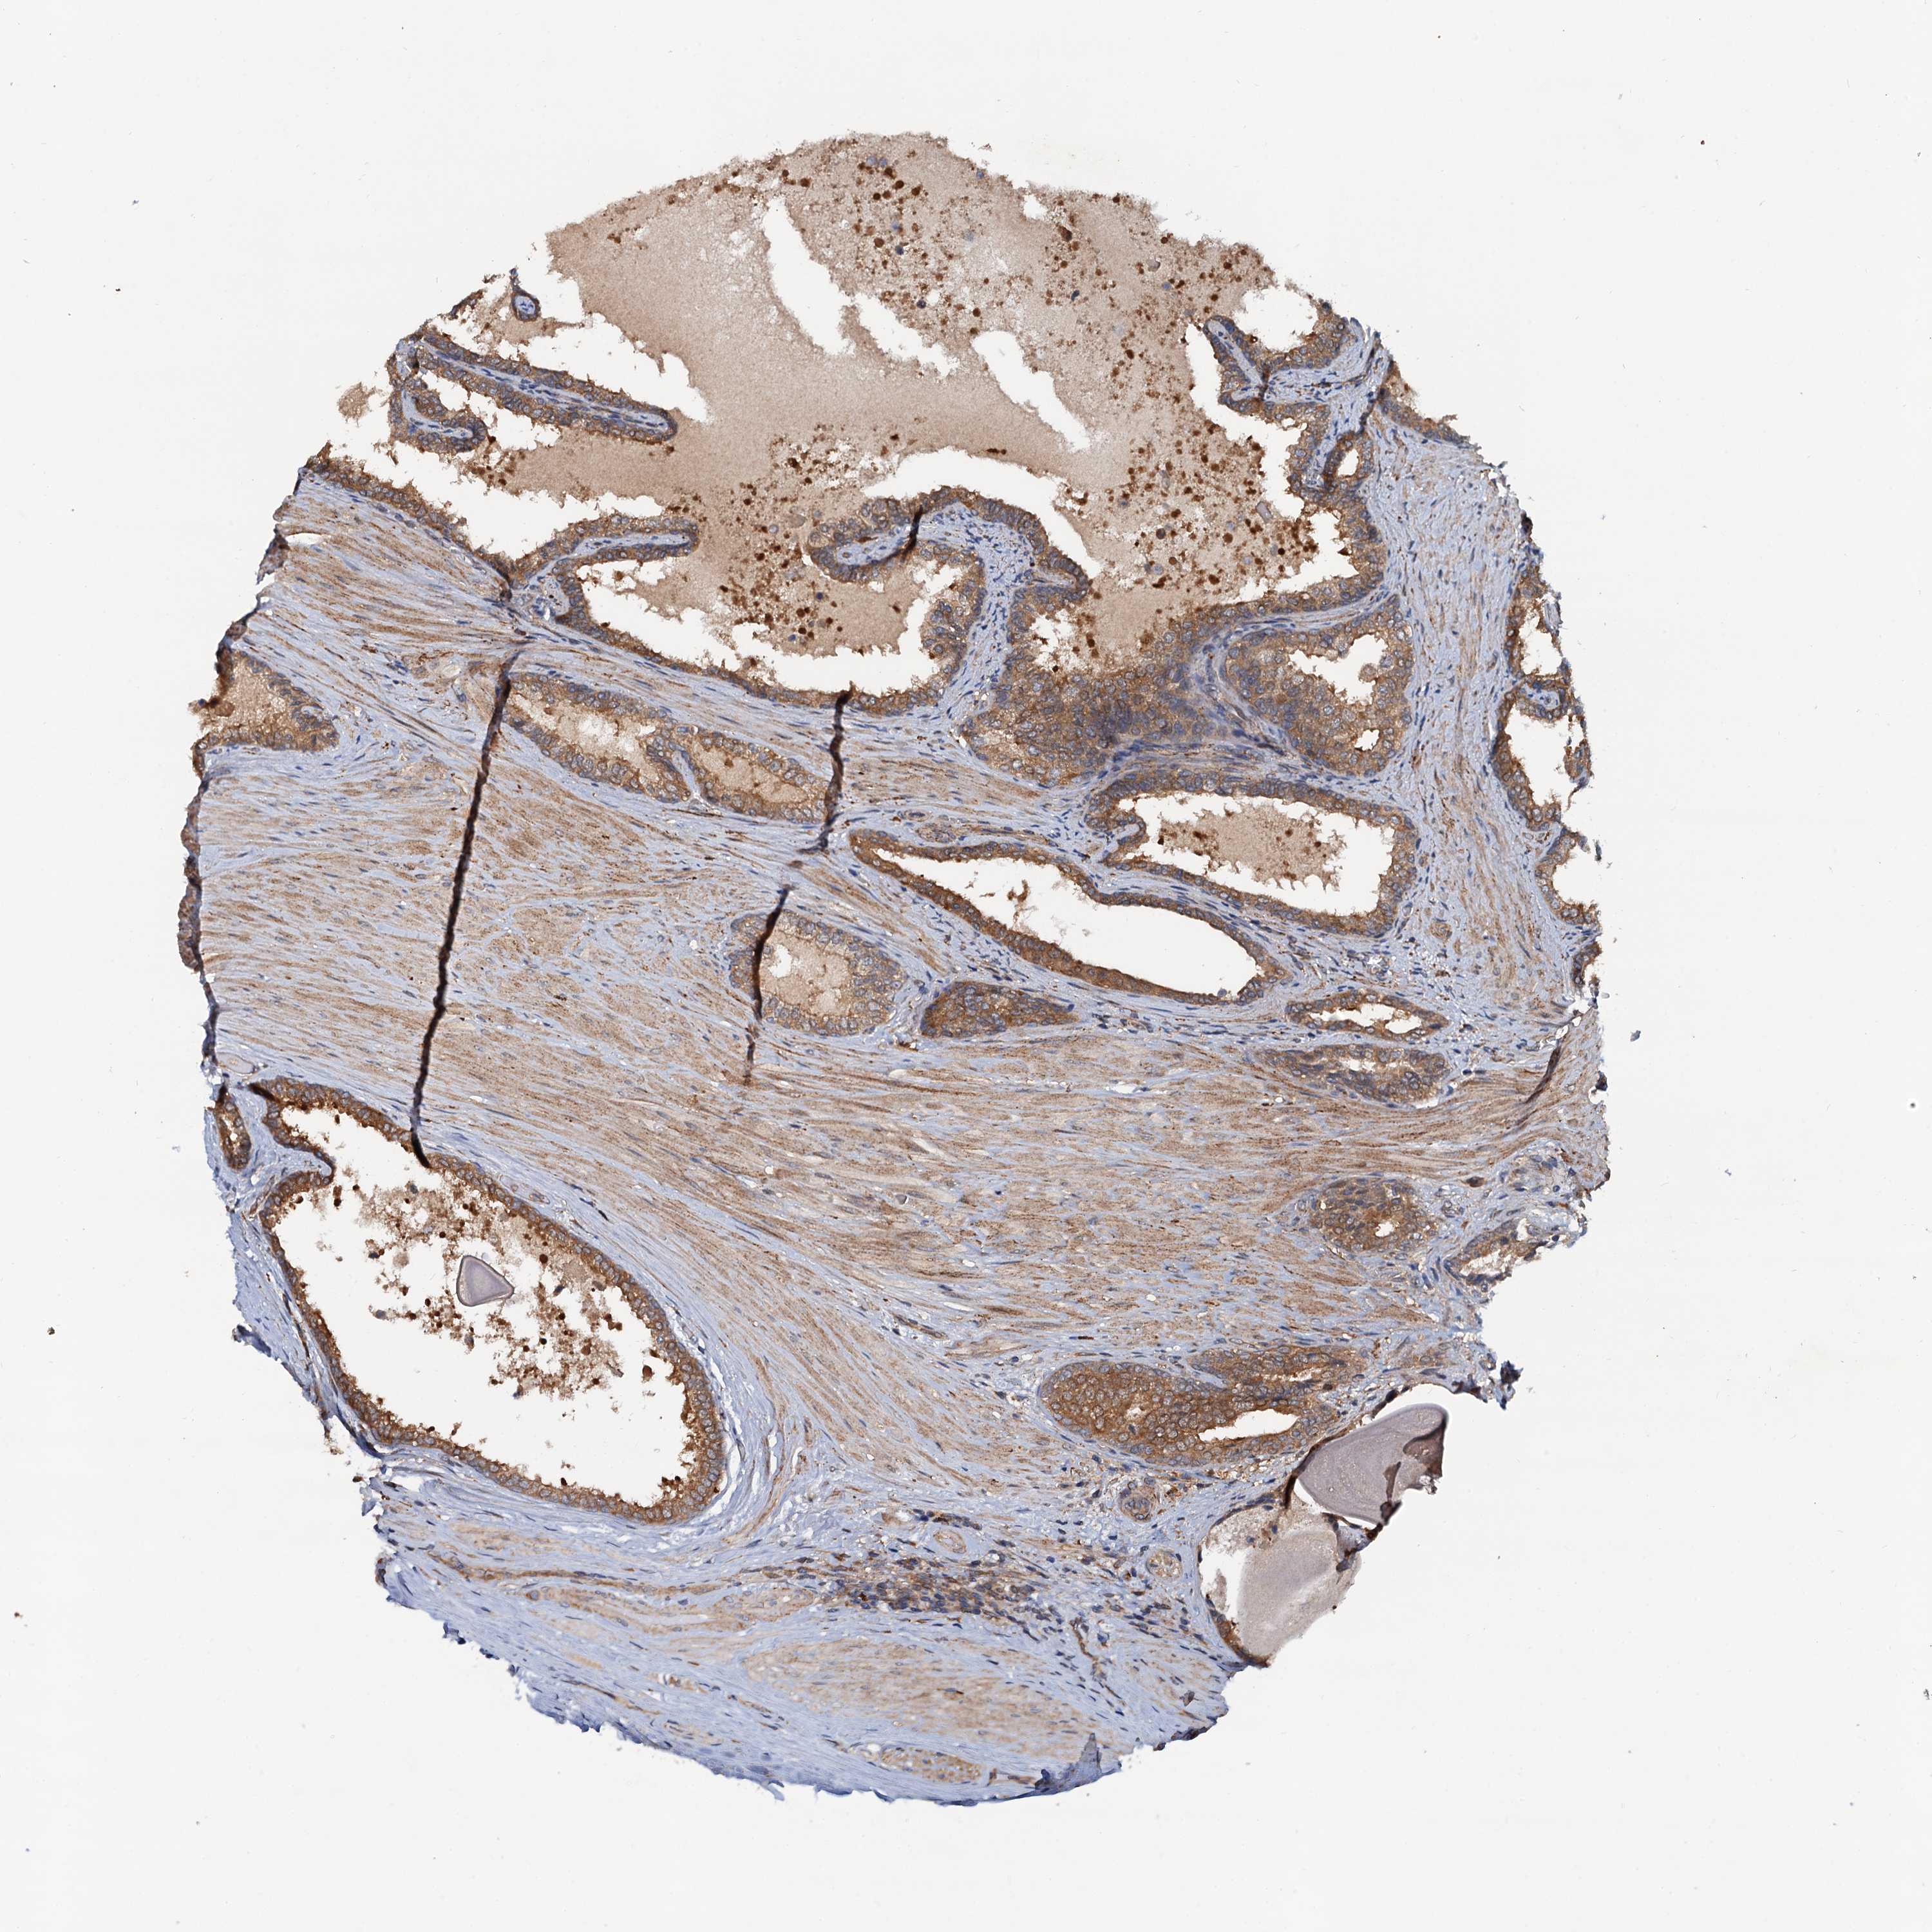

PROSTATE CANCER - Protein expressioni

A mouse-over function shows sample information and annotation data. Click on an image to view it in a full screen mode. Samples can be filtered based on level of antibody staining by selecting one or several of the following categories: high, medium, low and not detected. The assay and annotation is described here.

Antibody stainingi

Antibody staining in the annotated cell types in the current human tissue is reported as not detected, low, medium, or high, based on conventional immunohistochemistry profiling in selected tissues. This score is based on the combination of the staining intensity and fraction of stained cells.

Each image is clickable and will lead to virtual microscopy that enables deeper exploration of all samples and also displays staining intensity scores, fraction scores and subcellular localization as well as patient and tissue information for each sample.

Antibody HPA039371

Antibody HPA040174

Staining

High

Medium

Low

Not detected

Intensity

Strong

Moderate

Weak

Negative

Quantity

>75%

75%-25%

<25%

None

Location

Nuclear

Cytoplasmic/membranous

Cytoplasmic/membranous,nuclear

Adenocarcinoma, NOS

Adenocarcinoma, High grade

Adenocarcinoma, Low grade